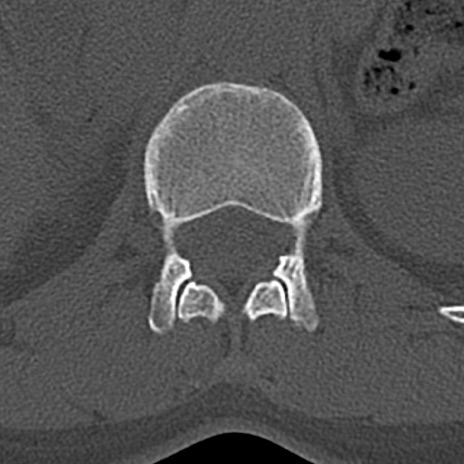

腰椎CT

横断像と矢状断像